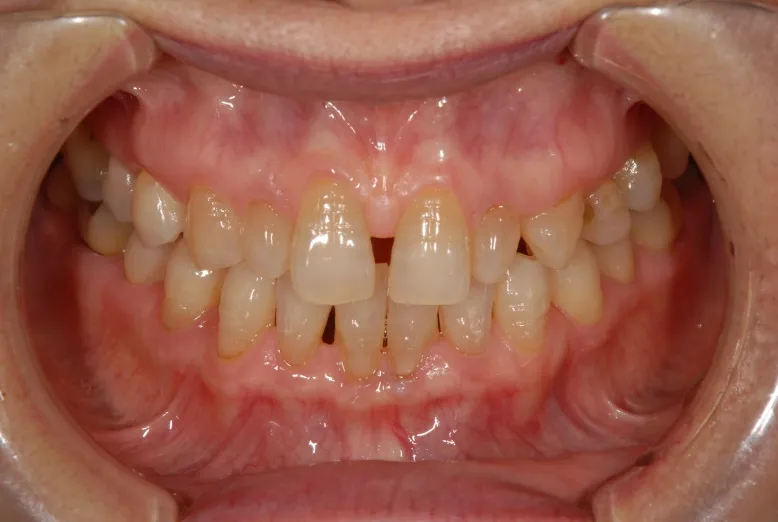

初診

歯石除去で来院されました。

除去後、話を聞くと上顎の前歯の歯と歯の間が離れていることが

以前より気になっていると仰られ、治療計画を立案。

口腔内写真の撮影

残っている歯の問題点などを解析

口腔内の分析・治療計画

さまざまな方向性から、歯のバランスや問題点を解析。

治療計画の立案を行います。